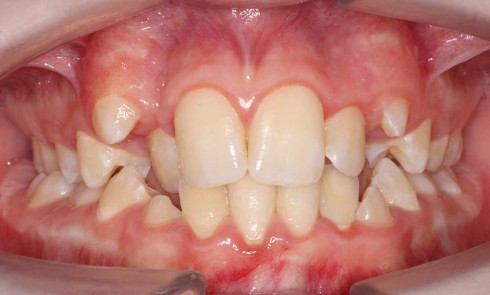

Alliah, en bonne santé générale, est adressée à un orthodontiste en 2010 par son dentiste généraliste en raison de la persistance des canines temporaires maxillaires alors qu’elle a 14 ans et que le reste de la denture permanente est évolué. Sa maman et elle sont toutes les deux convaincues qu’elle nécessite un traitement orthodontique pour corriger ce problème, ainsi que pour améliorer la position des incisives maxillaires qu’elles trouvent trop avancées.

L’harmonie du sourire n’est pas parfaite, avec une trop grande inclinaison vestibulaire des incisives maxillaires et un sourire gingival latéral disgracieux.

Examen endo-buccal

Le biotype parodontal est fin mais sans pathologie cliniquement décelable. Néanmoins, on note une hygiène bucco-dentaire qui nécessiterait d’être améliorée.

On peut considérer que le stade de denture est celui de la denture adulte jeune, malgré la persistance des canines temporaires.